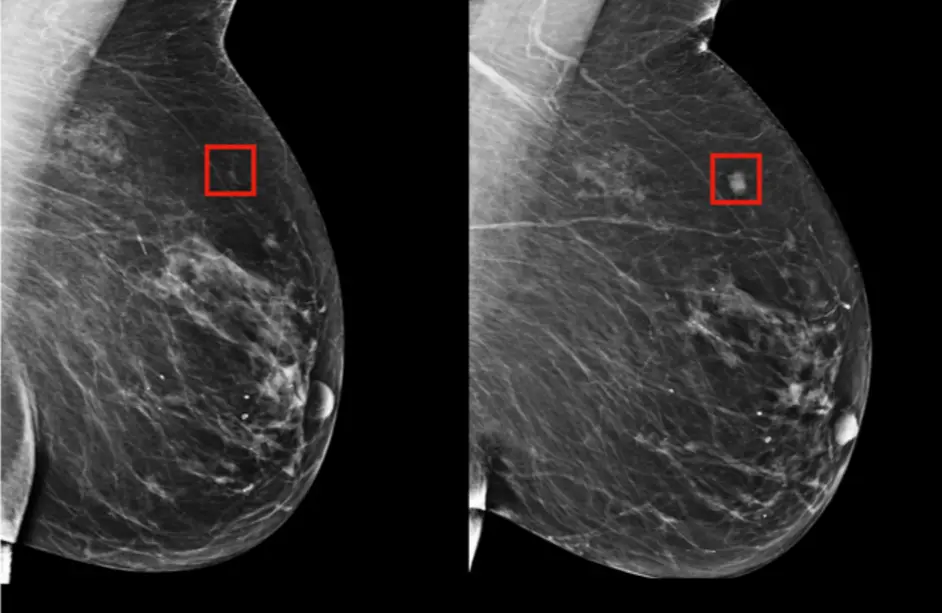

Meme Kanseri Taramasında Yapay Zeka